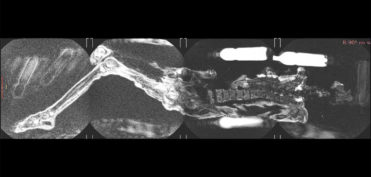

לאחרונה דווח על גבר בן 61 שמת בניו יורק לאחר שנמשך לעבר מכשיר MRI עקב שרשרת מתכתית גדולה שענד על צווארו. האירוע התר...